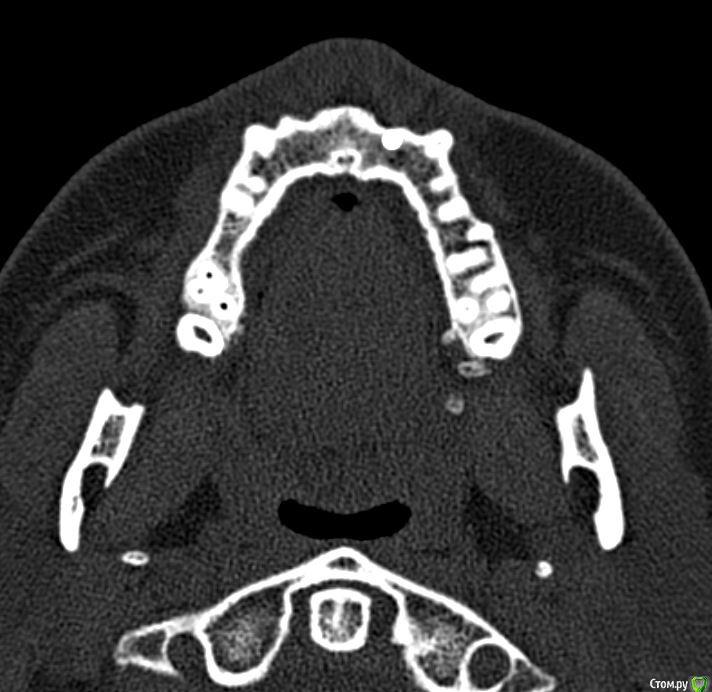

Лисица Опубликовано 26 июля, 2015 Автор Поделиться Опубликовано 26 июля, 2015 (изменено) Вы же не думаете, что Вам назначат а/б терапию по интернету? Я просто не знаю, исходя из каких показателей она назначается. Поэтому осведомилась на всякий случай. Итак, сходила я сегодня на КТ. И по ходу мне сделали что-то не то... Когда я обратилась в клинику, я уточнила, что мне нужно КТ для эндодонтии, чтобы видно было каналы, с достаточным разрешением, чтобы было видно зубы и их корни, входящие в верхнечелюстной синус. Администратор клиники уточнила у врача и сказала, что мне нужно заказывать не КТ верхней челюсти, а КТ пазух. У рентгенолога я также повторила все описанное, рассказала, что при лечении каналов вчера была продырявлена пазуха, уточнила, будут ли видны как следует зубы и их каналы, меня заверили, что "все будет". Причем у врача, судя по описанию на сайте клиники, была ординатура по хирургии в медико-стоматологическом университете, так что он, уж наверное, понимал, что мне нужно. В итоге я получила пленку со снимками формата чуть ли не А3 и диск. На пленке все зубы были просто белыми и коронки видны не целиком. Заключение: в правой верхнечелюстной пазухе уровень жидкости, острый правосторонний гайморит.Думала, может в программе можно будет увеличить разрешение. Но похоже, что нет... или я просто ламер? Зубы просто размытые и белые... Прилагаю сделанные мной скриншоты, как мне кажется, наиболее показательные... Если нужно другие "виды", то скажите какие, или такие снимки вообще ни о чем? Программа просмотра называется Philips DICOM Viewer R3.0-SP03. Аппарат был не местный "на голову", а здоровый, куда заезжаешь в лежачем положении. Изменено 26 июля, 2015 пользователем Лисица Ссылка на комментарий

Лисица Опубликовано 26 июля, 2015 Автор Поделиться Опубликовано 26 июля, 2015 Тьфу ты, Акелла промахнулся. Не та сторона в профиль. Вот парочка проекций с нужной больной стороны. Ссылка на комментарий

Лисица Опубликовано 26 июля, 2015 Автор Поделиться Опубликовано 26 июля, 2015 О, кажись я накопала настройки для более-менее понятного отображения Хоть и не уверена, что это то что нужно. Ссылка на комментарий

Лисица Опубликовано 27 июля, 2015 Автор Поделиться Опубликовано 27 июля, 2015 К сожалению, предыдущие сообщения уже не редактируются, но я наконец разобралась с правильным просмотром через DICOM Viewer Теперь у меня есть приличное 3D и я беру обратно свои слова насчет "неправильной" КТ %) Хотя все же нужно было делать челюсти, лобные доли мне как бы совсем ни к чему, а вот нижняя челюсть пригодилась бы...Думаю, как бы выложить DICOM-данные. Ссылка на комментарий

St. Опубликовано 27 июля, 2015 Поделиться Опубликовано 27 июля, 2015 Гайморит справа есть, и жидкость тоже. Корни этого зуба действительно заканчиваются в гайморовой.Ничего такого страшного, чтоб однозначно удалять зуб я не вижу. С гайморитом - к лорам на лечение.В зубе я бы ещё раз поменяла лекарство на пару недель, пока гайморит не притихнет, потом постоянно пломбировать. 1 Ссылка на комментарий

Лисица Опубликовано 27 июля, 2015 Автор Поделиться Опубликовано 27 июля, 2015 St., большое спасибо за ответ! Моя врач планировала закрыть его в среду (зная о том, что пазуха проткнута). Если запломбировать, пока воспаление есть, какие могут быть проблемы? И еще она сказала, что нащупала 4-й тонкий канал, но не было времени его прочистить, так что она оставила как есть до среды. Сказала, что почистит и сразу же закроет. Судя по КТ, корня 3, значит в одном из них 2 канала? В 3D похоже, что корни с медиальной стороны сросшиеся какие-то... и на небном тоже борозда. Ссылка на комментарий